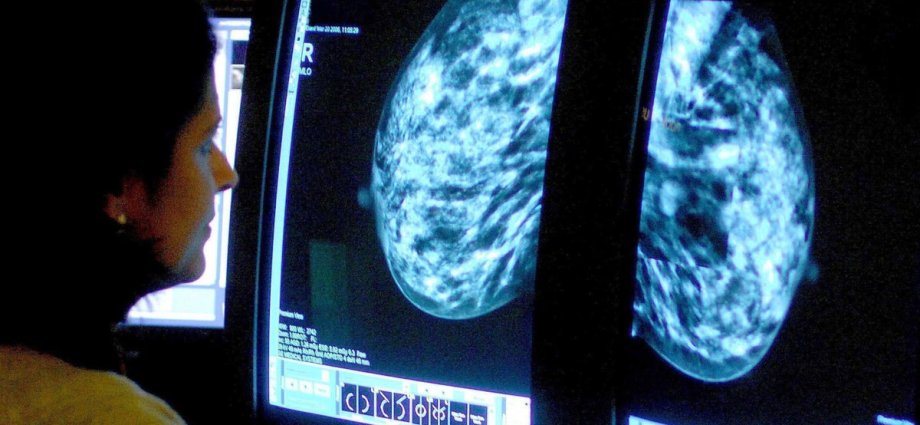

Two specialists are currently needed per mammogram screening, yet some cancers still go undetected. But using AI to help could mean just one specialist is needed to complete the same screening safely and efficiently – and it could even be more accurate.

It was then used to analyse the mammograms and triage low-risk cases to single reading and high-risk cases to double reading performed by radiologists. AI was also used as detection support to the radiologists, in which it highlighted suspicious findings in the image.